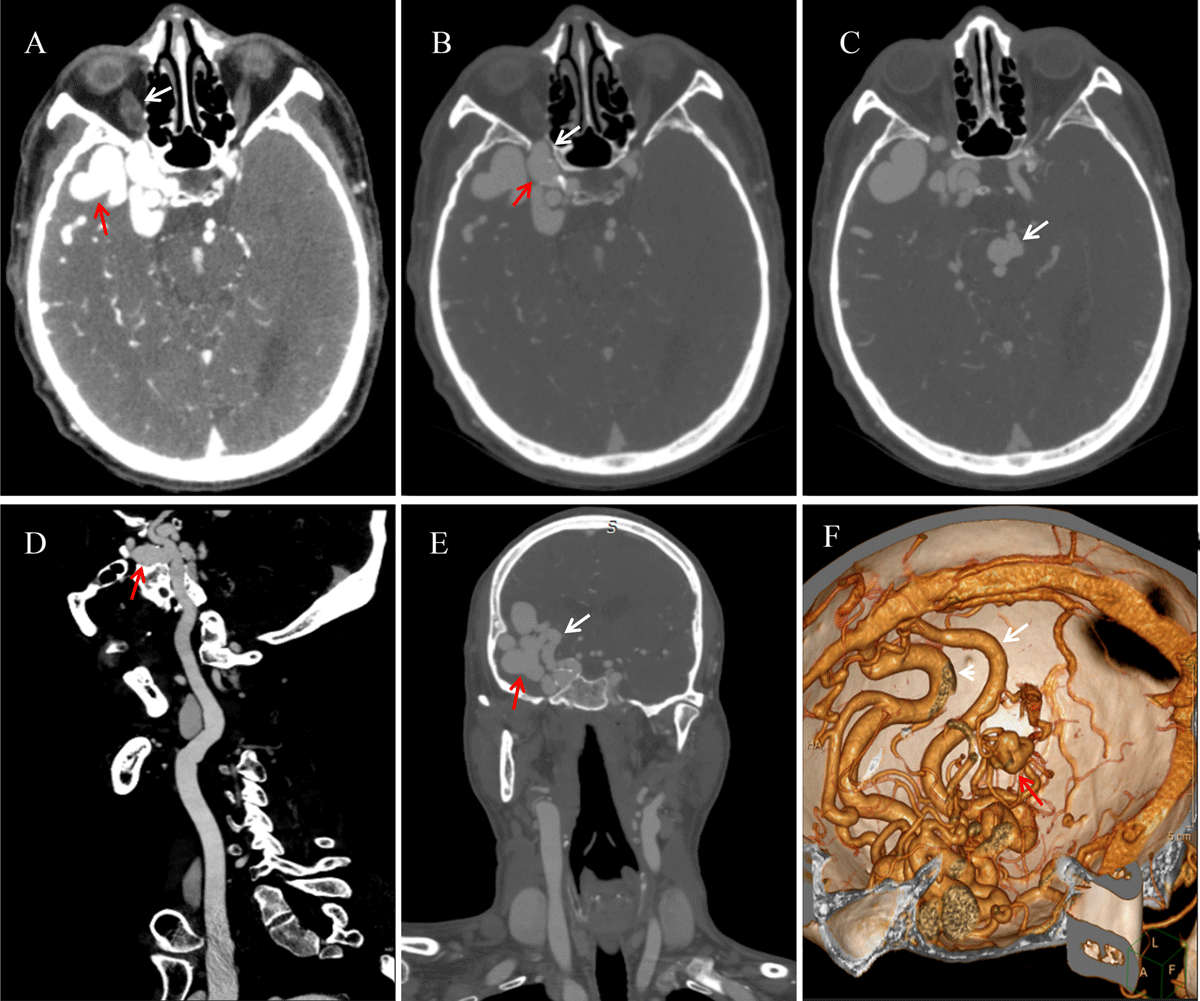

Figure 1

CTA presentation of intracranial arteriovenous malformation combined with multiple aneurysms.